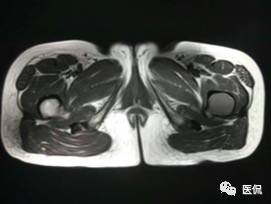

影像资料:

(3)MRI ABC的特征为鼓囊状的膨胀性破坏,呈单囊或由低信号的间隔分隔成大小不等的多囊。因血细胞和血浆的分离和沉淀,囊内可见液-液平面。在T2WI上,液面上层为高信号,下层为低信号;T1WI上则相反,上层为低信号,下层为偏高信号。液-液平面是ABC较特征的征象。增强检查低信号的纤维间隔呈环形强化。继发性动脉瘤样骨囊肿可在其原发病灶内有液-液平。